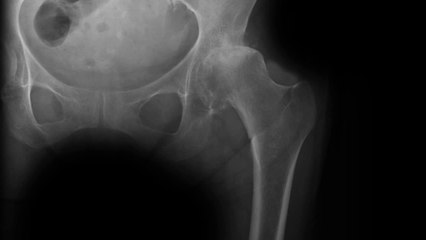

RCS doesn't welcome rationing of hip and knee replacements

The Royal College of Surgeons does not welcome NHS plans to ration hip and knee replacements. Report by Duffys.